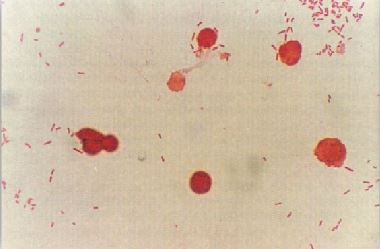

بعد فترة وجيزة من عودته من أفريقيا بدأت صحة هذا المريض في التدهور وعاني من سعال وارتفاع في درجة الحرارة مع إمساك بعد ذلك ازدادت حالته الصحية سواءاً بعد عدة أيام وأصبح يعاني من إسهال، بالكشف عليه تبين وجود طفح جلدي وتضخم الطحال. عدد كريات الدم البيضاء 4.0 X 109 / لتر ، تم زراعة عينة من الدم على الوسط الغذائي المناسب كما في الشكل 1 كما زرعت عينة من البراز على الوسط الغذائي المناسب كما في الشكل رقم 2 .

الشكل رقم 1 : الفحص المجهري

الشكل رقم 2 : المزرعة البكتيرية

1- حالة هذا المريض تعرف بحمى التيفود typhoid fever وتستغرق فترة الحضانة حوالي 14-10 يوم ، ومن صفات هذا المريض ان الشخص المصاب يعاني في البداية من إمساك ثم سرعان ما يتحول إلى إسهال إذا لم يعالج المريض ومن العلامات التي تساعد على التشخيص السريري للحالة هو تكون ما يعرف بالبقع الوردية rose spots على الصدر والأكتاف وكذلك تضخم الطحال ونقص في كريات الدم البيضاء. يعتبر النوع البكتيري Salmonella typhi المسبب الرئيسي لهذه الحالة وهذه البكتيريا تنتقل عن طريق الماء الملوث بالفضلات الآدمية وبالتالي فإن الماء يلعب دوراً مباشراً في إحداث المرض أو غير مباشراً وذلك عند استعماله في غسيل الخضراوات وما شابه ذلك وبعد ابتلاع هذه البكتيريا تبدأ في دخول الطور الابتدائي الموضعي وهو التكاثر داخل خلايا النسيج الليمفاوي للأمعاء الدقيقة ثم يعقبه وصول البكتيريا للدم bacteraemic phase وهو الطور الثاني وتواصل التكاثر فندخل الطور التالي وهو طور تجرثم الدم septicaemic phase فنبدأ البكتيريا في الانتشار داخل الجسم لتصل لأعضاء مختلفة من الجسم فقط يصاب المريض بمرض التهاب السحايا أو التهاب الرئة أو التهاب العظام وأمراض اخرى. وإن تواصل يجب إبلاغ السلطات المختصة بالأمراض السارية حول الحالات التي يتم تشخيصها.

2- غالباً ما يتم عزل هذه البكتيريا في الأسبوع الثاني أو الثالث من حدوث المرض بزراعة عينة من الدم كما يمكن زراعة عينة من البول أو البراز ، وكذلك يمكننا عزلها من عينة البصاق وسائل النخاع الشوكي ويتم استعمال الوسط الغذائي التفريقي DCA أو XLD وفي وسط غذائي مغذي وهو حساء Selenite F broth بعد مضي فترة التضحين تظهر مستعمرات باهتة اللون (نتيجة لعدم قدرتها على تخمير سكر اللاكتوز) وقد تظهر سوداء اللون نتيجة لتكون المركب كبريتات الهيدروجين hydrogen sulhide كما في الشكل رقم 2.25. وبعد ذلك يتم إجراء الاختبارات الكيموحيةي والمصلية للتأكد من التعريف. وهذا المرض قد يسببه النوع البكتيري S. paratyphi من النوع A ، B أو النوع C بالإضافة للنوع البكتيري S. typhi كما أنه ناذراً ما يكون ناتجاً من الإصابة بالنوع البكتيري S. choleraesuis .